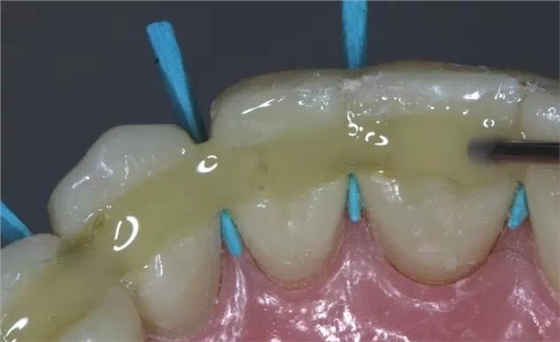

牙周炎發(fā)展到一定階段時(shí),僅采用基礎(chǔ)治療難以取得較好療效,必須通過適時(shí)而合宜的手術(shù)治療挽救患牙,才能保持牙周組織健康,延長患牙在口腔內(nèi)的壽命,維持牙列的完整性,促進(jìn)全身健康。其手段包括齦下刮治、根面平整、牙周翻瓣術(shù)、牙齦切除術(shù)、牙周夾板固定術(shù)等。